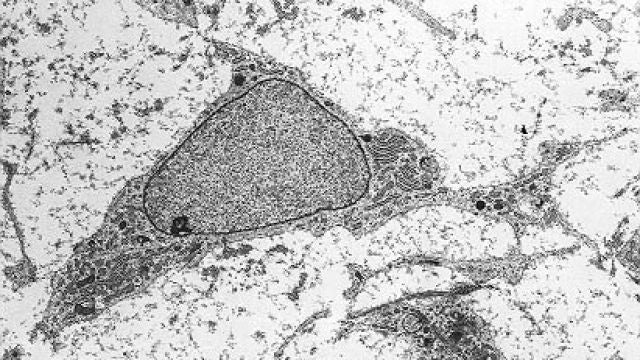

Células madre mesenquimales Sinc

Estudios previos en animales y humanos habían sugerido el potencial de las células madre mesenquimales de la médula ósea, también conocidas como células estromales o MSC –por sus siglas en inglés– en el tratamiento del lupus, ya que se considera que la enfermedad puede ser producto de una alteración en el tejido mesenquimal, aquel que da lugar, por ejemplo, a huesos, músculos o cartílagos.